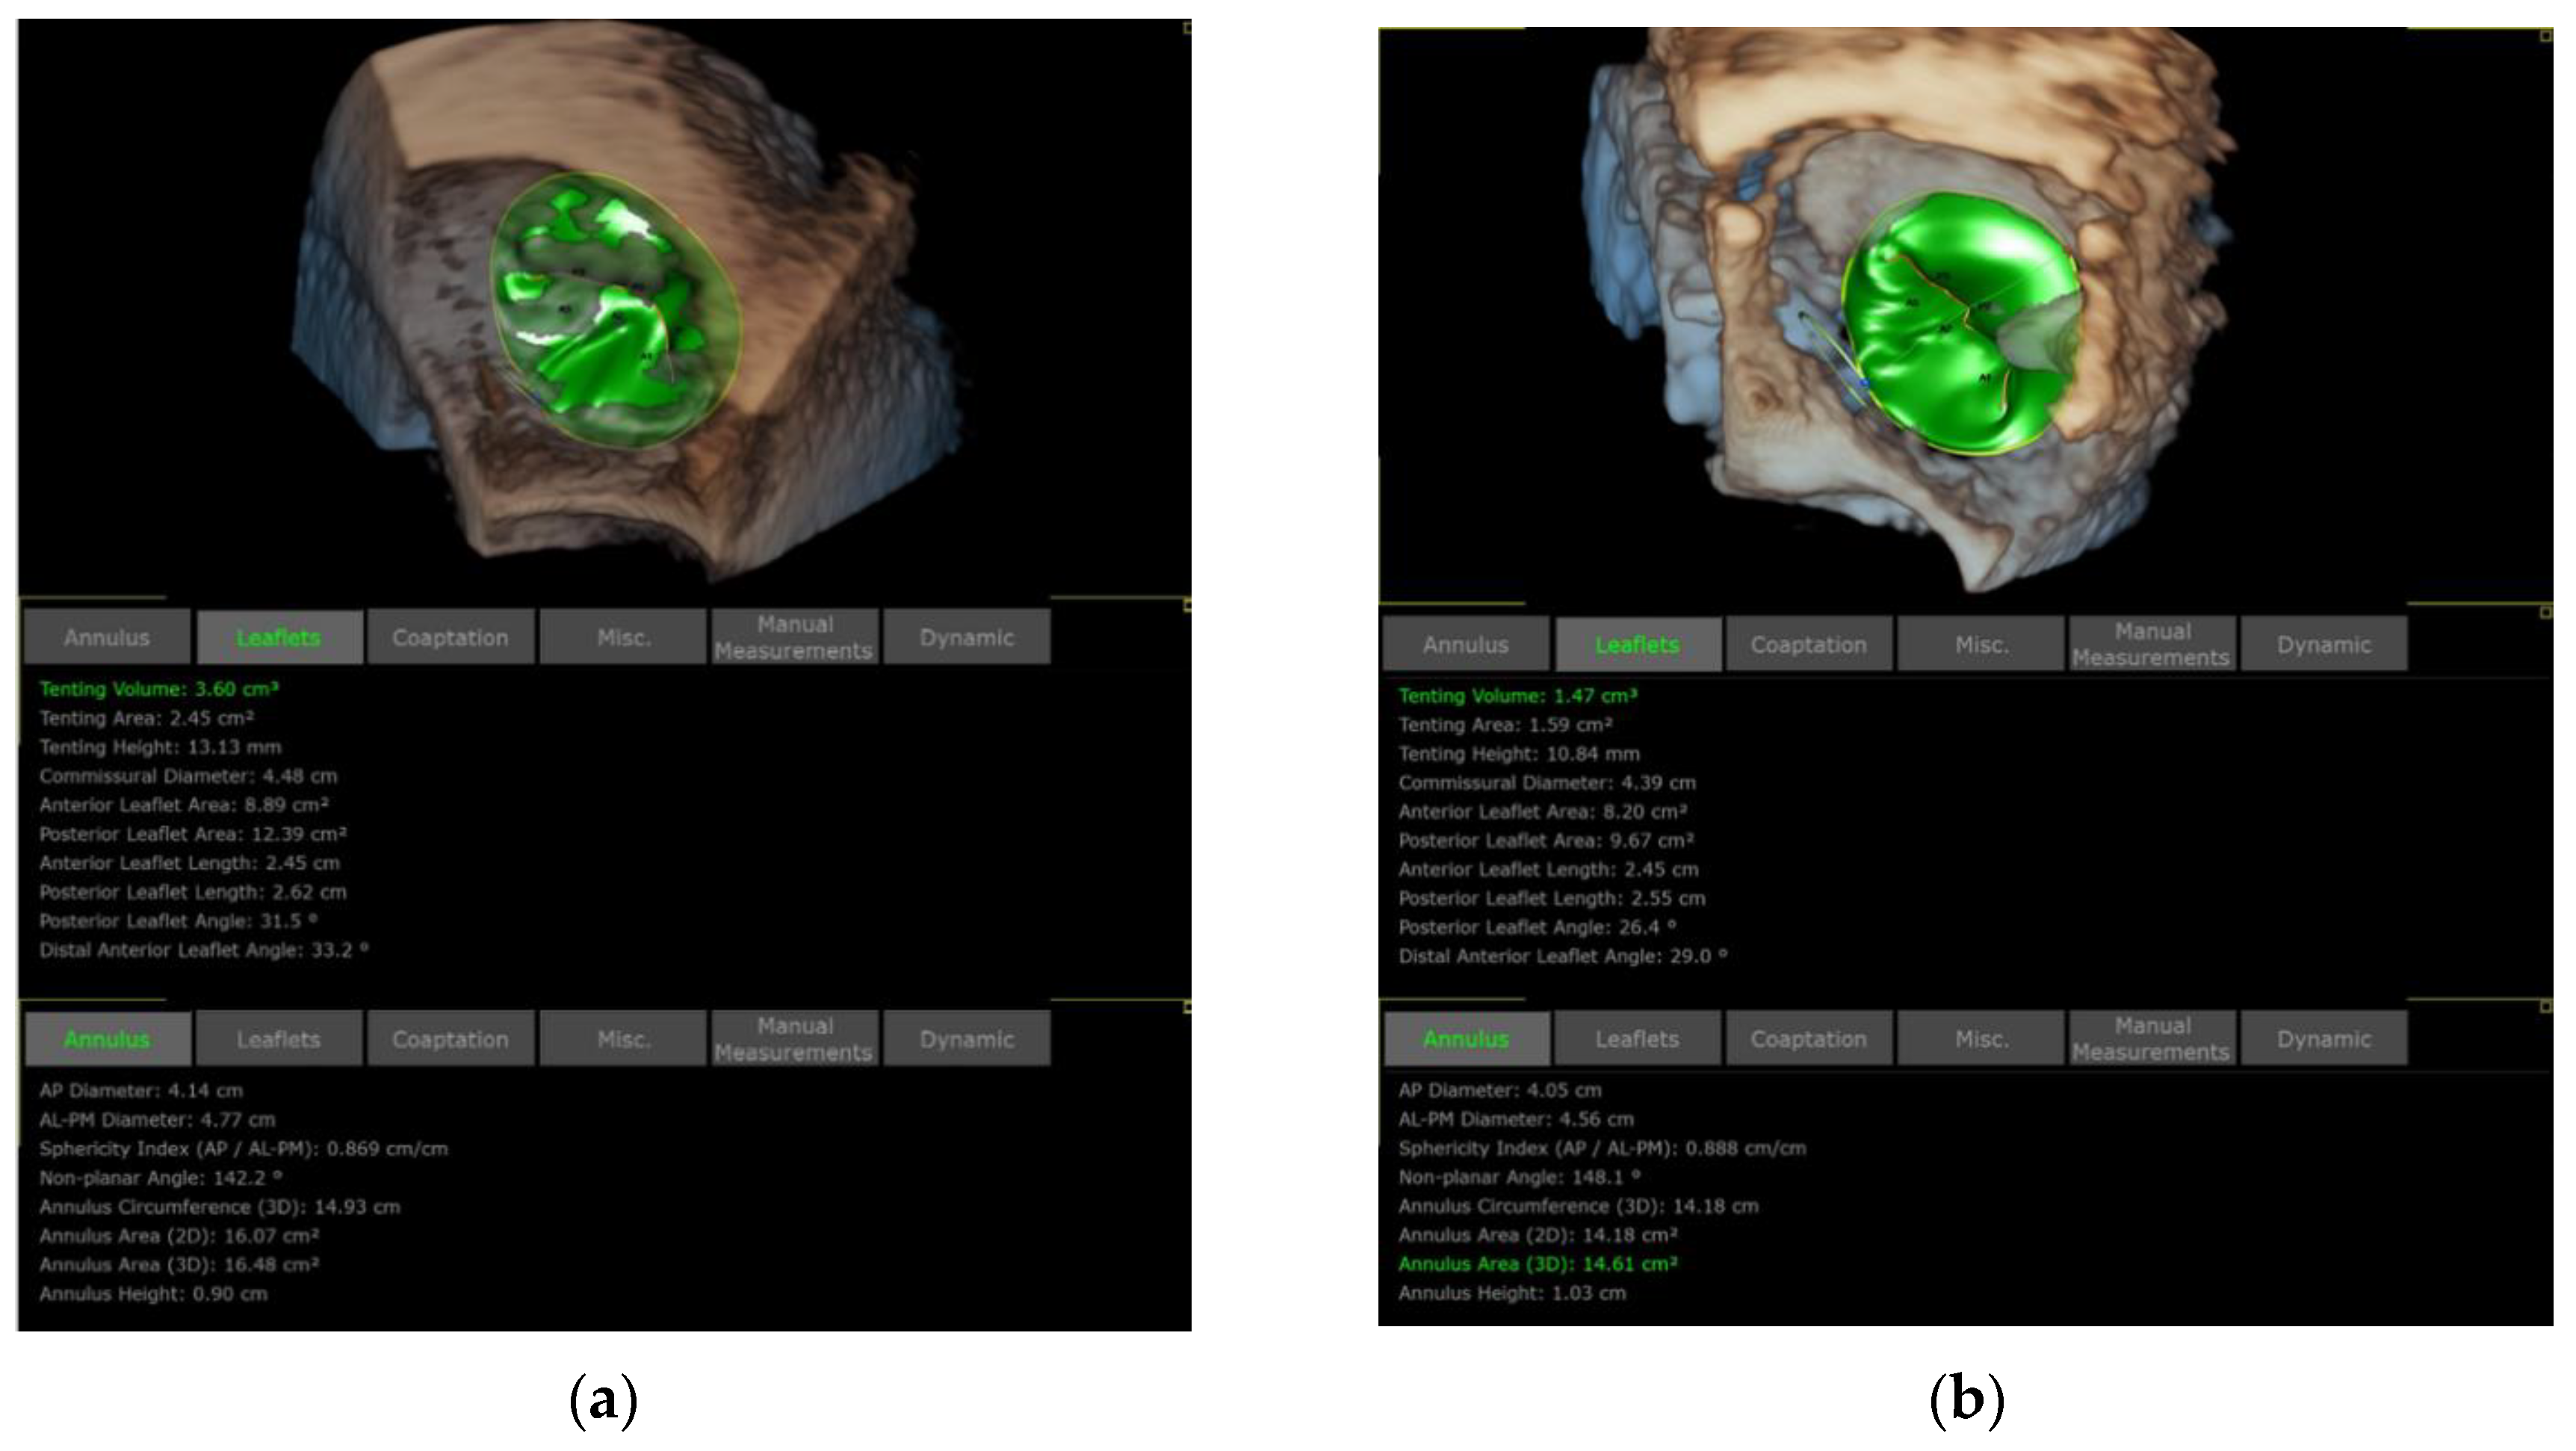

3.1. Patient Selection

3.5. Valve Function Assessment